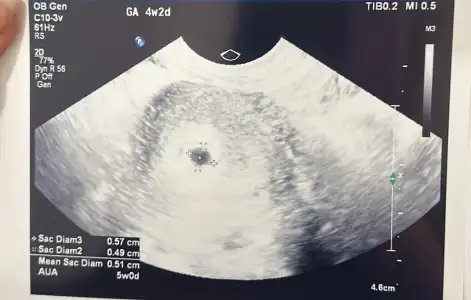

Sat 6 mart Bat 2 nisan.

Dayanamayıp kan verdim, beta hcg 5.6ymış

Dün çatlamanın üzerinden geçen 8. Gündü, gebelik varsa zaten anca 5.6 olabilirdi beta